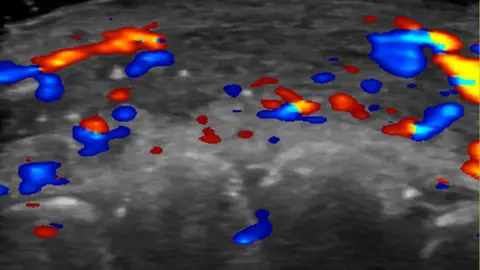

Researchers used ultrasound to study 100 cases of filler injections that had gone wrong.

In just under half the cases, ultrasound scans showed absent blood flow to small blood vessels that connect superficial arteries to deep ones in the face.

And in a third of cases, blood flow was absent in major blood vessels.

To avoid complications in the first place, she advises clinics to use ultrasound to plan where to inject.

If complications do arise, ultrasound can guide where to treat.

“If injectors are not guided by ultrasound, they treat based on where the clinical findings are and inject blindly,” Dr. Sigrist says.

“But if we can see the ultrasound finding, we can target the exact place where the occlusion occurs.”